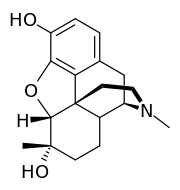

Dihydromorphine Dihydromorphine |